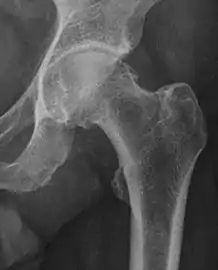

| Crossing ratio | ![]() |

Percentage of acetabular walls crossing. Normal acetabulum is oriented in anteversion. Its value ranges from 15 to 20° in the equatorial plane of the acetabulum and decreases gradually towards the acetabular roof, where normal values range from 0 to 5°. Retroversion of the upper part of the acetabulum has been related with pincer type impingement. In radiography the presence of a "crossover sign" is produced when the posterior wall of the acetabulum crosses the anterior wall before reaching the acetabular roof. It is a sign of acetabular retroversion and it has been linked with overcoverage and pincer impingement. Nevertheless, this sign has been described in 6% of the normal population. Therefore, more important than its presence is the percentage of crossing. | <20%

|